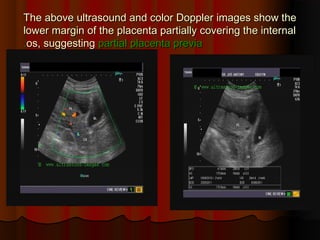

The above ultrasound and color Doppler images show the

lower margin of the placenta partially covering the internal

os, suggesting

os, suggesting partial placenta previa

partial placenta previa

.